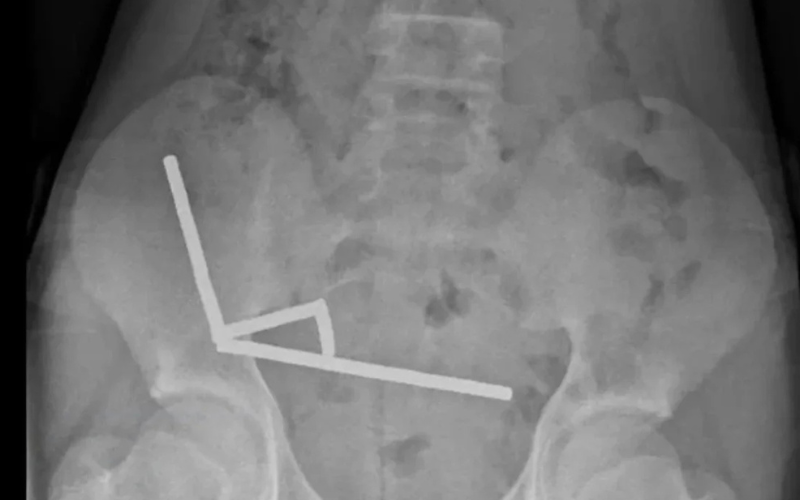

Хлопчика госпіталізували після чотирьох днів болю в животі. Рентген показав, що магніти утворили всередині кишківника чотири прямі лінії, скріплені магнітними силами, що спричинило відмирання тканин. Хірурги провели операцію та видалили магніти й уражені ділянки кишківника. Дитина після восьми днів перебування у лікарні повернулася додому.